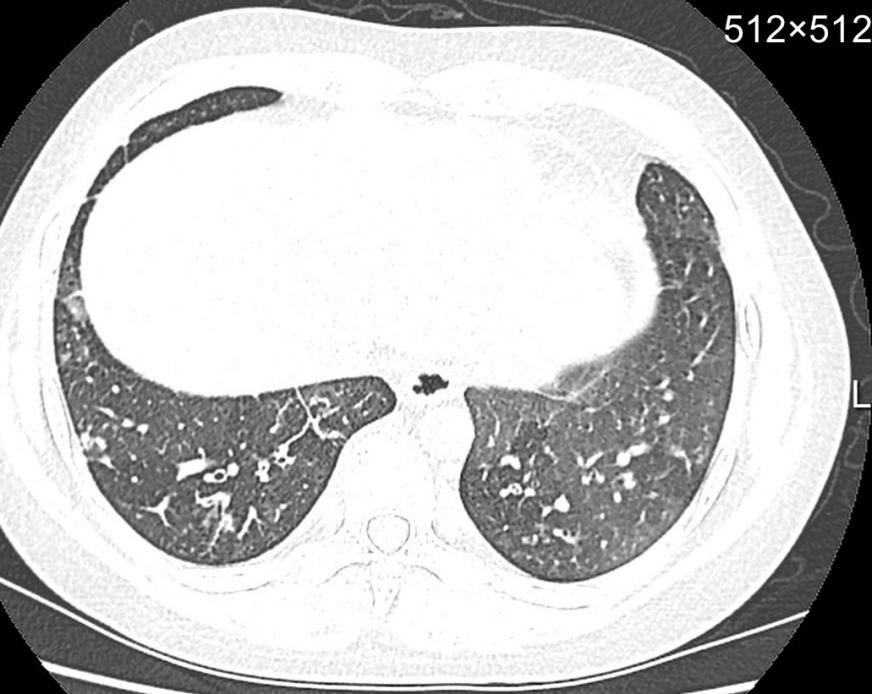

一是磨玻璃影,这是早期甲流肺炎的典型表现之一。在CT影像上,肺部会出现类似“薄雾笼罩”的半透明阴影,提示肺泡内有少量炎性渗出物。这种病变多位于肺部外周区域,早期可能范围较小,若未及时干预会快速扩散。二是斑片状或大片状实变影,随着病情进展,炎性渗出物增多,肺泡被填充,影像上会出现密度增高的片状阴影,严重时可累及多个肺叶。三是肺部纹理异常,轻症感染者可能仅表现为肺部纹理增粗、模糊,提示支气管黏膜存在炎症反应。少数重症患者还可能出现胸腔积液、肺不张等并发症,在影像上可观察到胸腔内液体增多、肺部组织塌陷等表现。

CT横断面示例